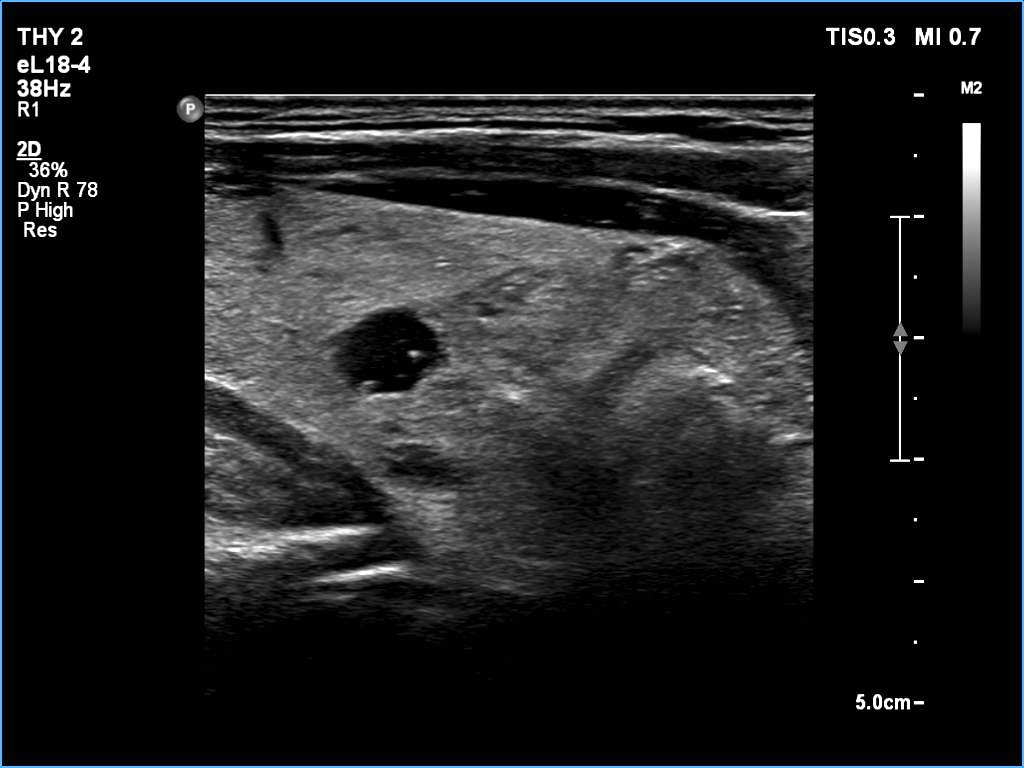

Ultrasonography: The thyroid was echonormal. There was a larger nodular mass in the right lobe which was composed of a dominantly solid echonormal portion that surrounded a dominantly cystic area. There were multiple nodules in the left lobe. The latter included an almost completely cystic lesion.

Comment. The right nodule is dominantly solid one because the cystic portion is less than 50%. The cystic portion of the nodule is multichambered which presents spongiform areas. The left cystic nodule is an almost completely cystic lesion, that has disappeared after the removal of cystic fluid.